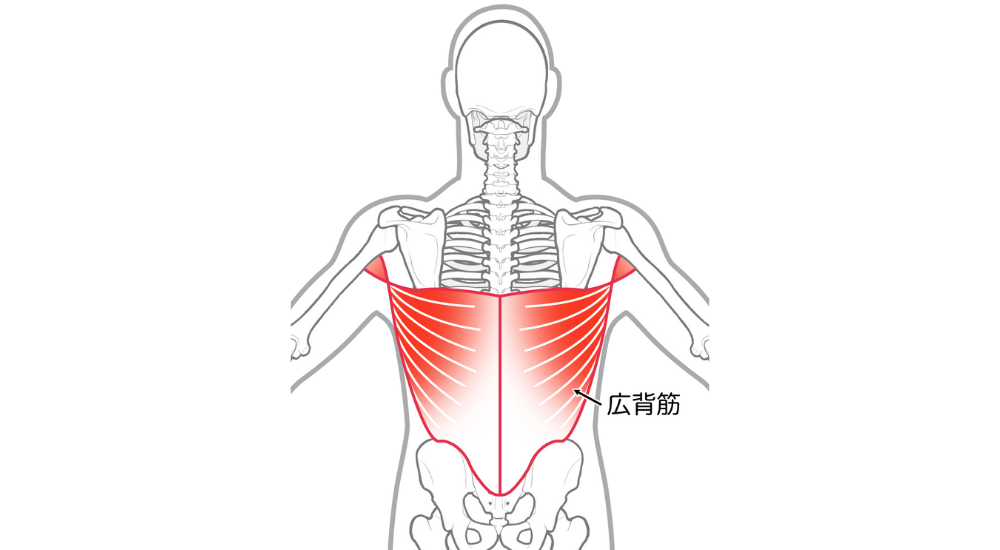

- 広背筋:

非常に大きな筋肉で、脇の下から背中、腰まで付着する筋肉です。猫背反り腰を誘発し、腰の痛みに関与します。